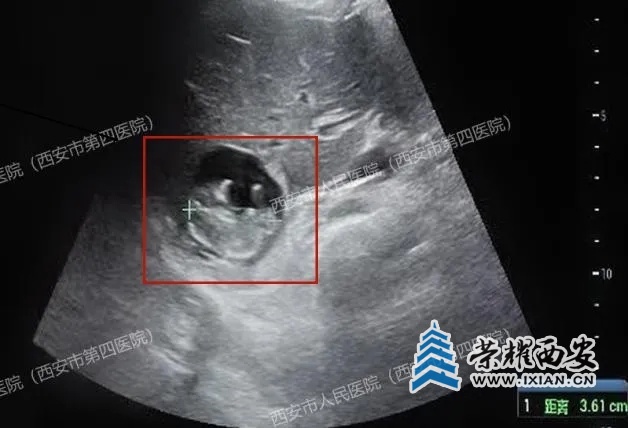

医生觉得疑惑,耐心安抚患者的同时又全面细致的沿子宫周围及上方扩展了扫查范围,当扫查到肝脏时,顿时惊呆了......胎儿竟然长在了肝脏上!!!

胎心搏动强劲有力,胎盘雏形也已形成,测量的顶臀径约36mm,估算的孕周近11周了!

(肝右叶有一个47x35mm的囊实性占位,附件区包块影像显示为卵巢巧克力样囊肿,并非妊娠囊)